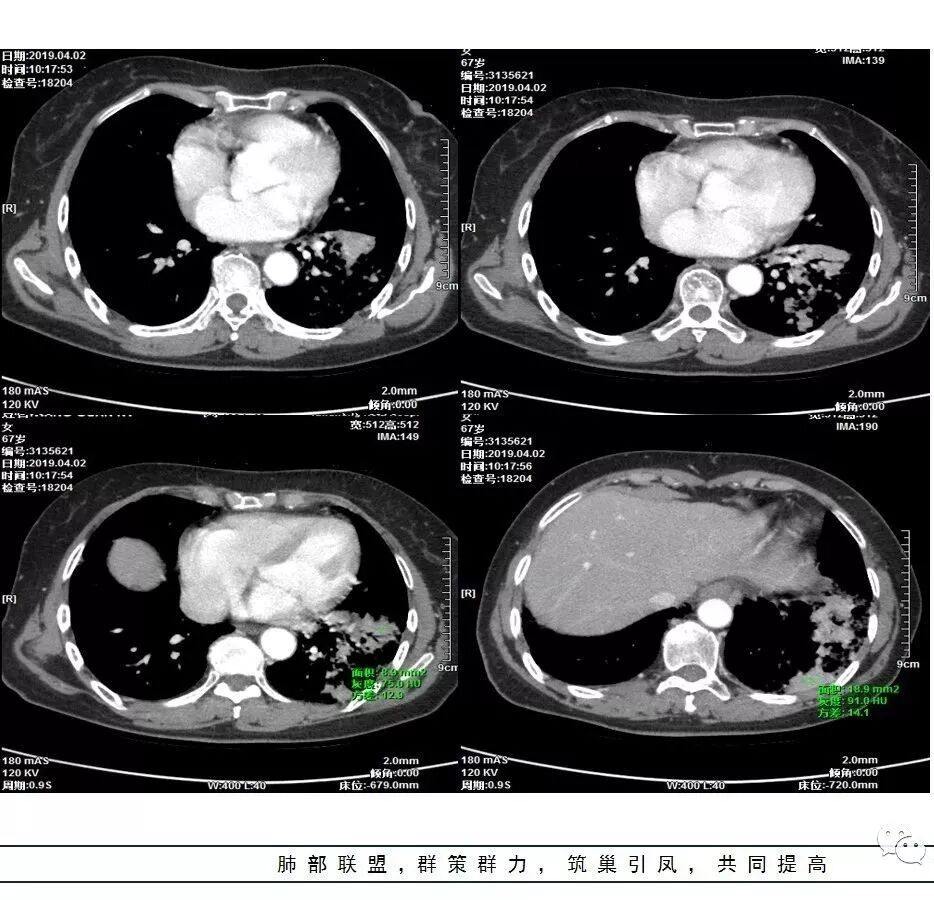

这是老问题:1、肺门区软组织密度影较弥漫;我们常规鉴别的就是结核?鳞癌?既往我们群里基本这两方向。2、弥漫的淋巴结钙化,加上马赛克灌注。马赛克灌注的原因是两个,一个是肺动脉的,一个就是小气道的问题。我们看增强的区域,没有看到栓塞,所以我倾向于小气道的问题,就是弥漫气道病变,慢性气道病变要考虑。我怀疑有没有淀粉样变性累及气道壁改变的可能。淀粉样变性是一个继发性病变,结核也可以,粉尘也可以。

这个病例支气管狭窄后扩张,肺门区有很多钙化的淋巴结,两肺弥漫的马赛克灌注,肺门淋巴结这么多,一个结核,一个尘肺,然后就是一个淀粉样变性,这几种最常见。鳞癌因为老年女性,除非吸烟,不太考虑,又不能绝对排除,所以就把鳞癌放到后。

实变部分强化很明显,怎么解释合理呢

结核强化可以这样吗?

肉芽肿期强化明显

肉芽肿是一个病理的概念,是炎症后期的修复,它的本质其实是迟发型过敏反应引起的炎症,在免疫应答中主要是一些巨噬细胞、上皮细胞来起作用,但是里面有非常丰富的毛细血管,所以这类病变强化很明显,影像上一般是结节状、团块状、大片状,整体有膨隆,边缘也有收缩,肉芽肿是一大类,影像有时很难区分,尘肺、结节病、淋巴瘤样肉芽肿都可以。常见的是炎性的,多见于结核,细菌性感染后期引起的类似op样,影像统称肉芽肿类病变,鉴别炎性还是恶性,要根据边缘、形态、周围结构及内部坏死情况。

今天这个病例有个明显的支气管狭窄,我倾向炎性,主要是和钙化淋巴结相关的,可能是继发的淀粉样变性。到底是什么感染,结核还是其他。我想看看复查后这个淋巴结,有没有突入到支气管腔内,如果有,他是继发于炎症的(比如中叶综合征,就是周围淋巴结压迫支气管,因为钙化淋巴结比较硬,支气管壁扛不住压力,突入支气管腔内,导致管腔狭窄,我们也称为结石征),如果没有,就和淋巴结关系不密切。之前有一例淀粉样变性的,淋巴结弥漫钙化,一种罕见的浆细胞型的CD。